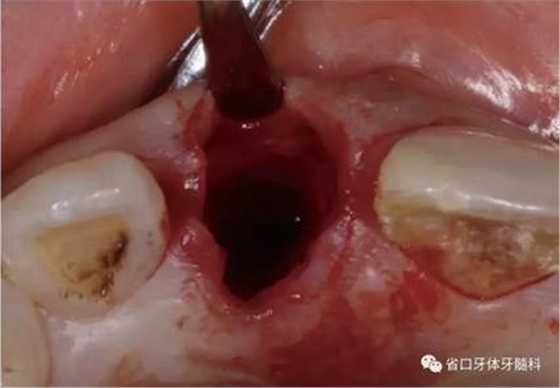

圖11 三棱鉆定位

圖12 平行桿檢查

圖13 平行桿檢查

圖14 平行桿檢查

(1)微創(chuàng)拔牙及即刻種植:術(shù)前拍攝口內(nèi)照及實(shí)施牙周基礎(chǔ)治療。常 規(guī)消毒鋪巾阿替卡因局麻下微創(chuàng)拔除上頜右側(cè)中切牙,搔刮拔牙窩及根尖肉 芽組織。探測牙槽骨唇側(cè)骨壁及鄰面牙槽嵴完整,牙齦無撕裂。不翻瓣下于上頜右側(cè)中切牙缺隙近遠(yuǎn)中中點(diǎn)的腭側(cè)牙槽骨及根方定位,按照逐級預(yù)備的原則,緊貼牙槽窩腭側(cè)骨壁制備種植窩洞,植入Zimer®3.7mm×13mm TSV種植體1顆,植入扭矩>35N·cm,以O(shè)sstell測量種植體的ISQ值為68。 種植體平臺位于唇側(cè)齦緣中點(diǎn)下3mm,與唇側(cè)骨壁內(nèi)側(cè)面形成的跳躍間 隙約2mm,置入Bio-Oss®細(xì)顆粒骨粉0.25g,上愈合基臺關(guān)閉創(chuàng)口。術(shù)后 CBCT檢查顯示:種植體利用牙槽窩根方骨質(zhì)固位,緊貼牙槽窩腭側(cè)骨壁, 其唇側(cè)面與牙槽窩唇側(cè)骨壁的內(nèi)側(cè)面所形成的跳躍間隙(約2mm)可見顆 粒狀顯影物充填。牙槽窩的唇側(cè)骨壁及唇側(cè)倒凹無缺損穿孔。